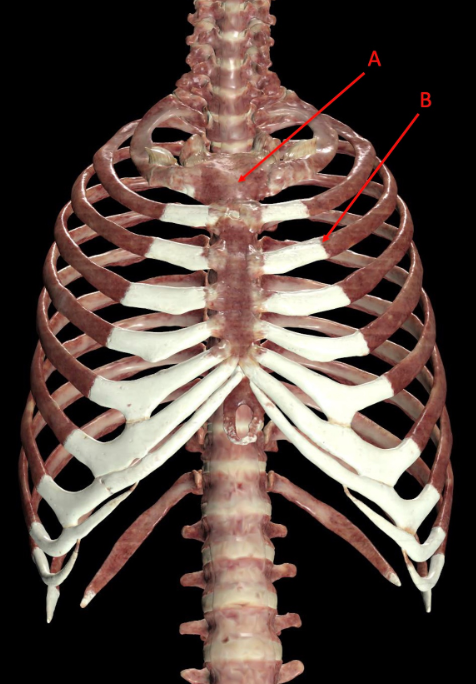

A. costotransverse joint, allows gliding movement

B. floating rib, protects thoracic organs and provides attachment points to muscles of back, chest, proximal upper limb